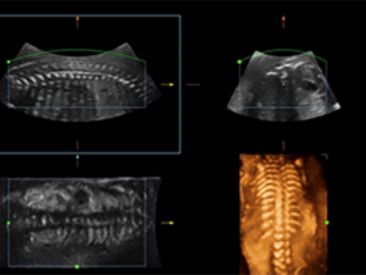

SoluciĂłn de volumen doble DE11-3E

ImĂĄgenes clĂnicas